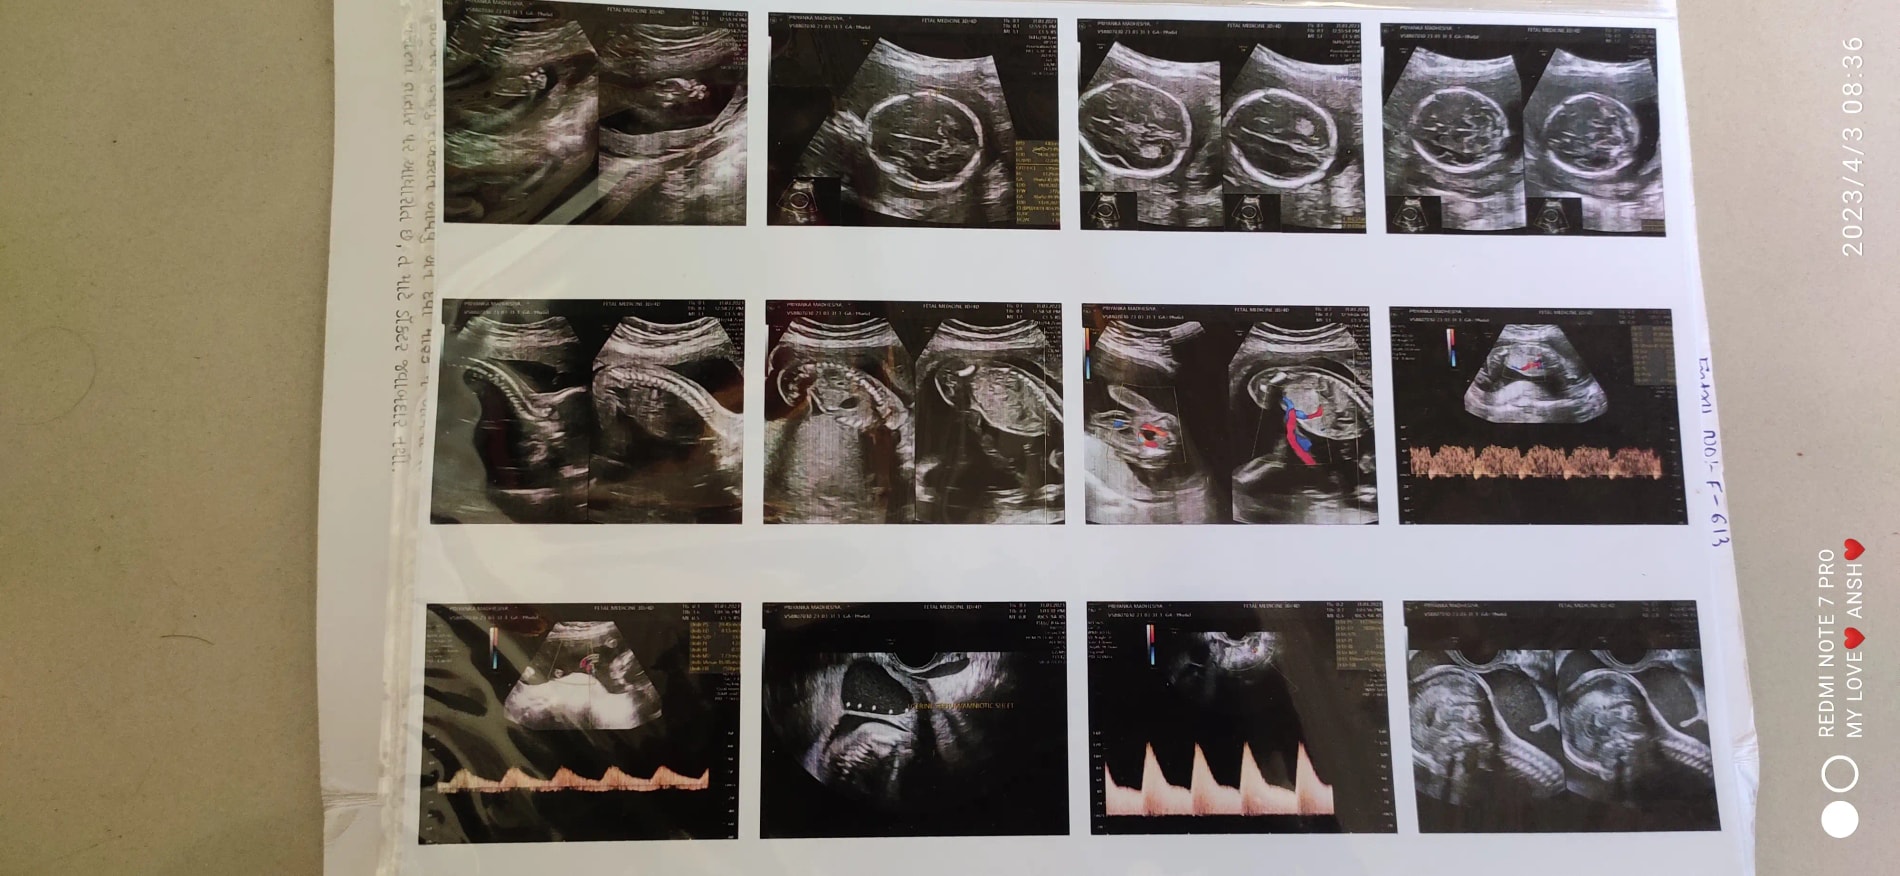

Q: Sonography me ye kya box jaisa doctor bol Raha hai

A: Written report dijiye yah dekh kar samajh mein nahin aata... See more